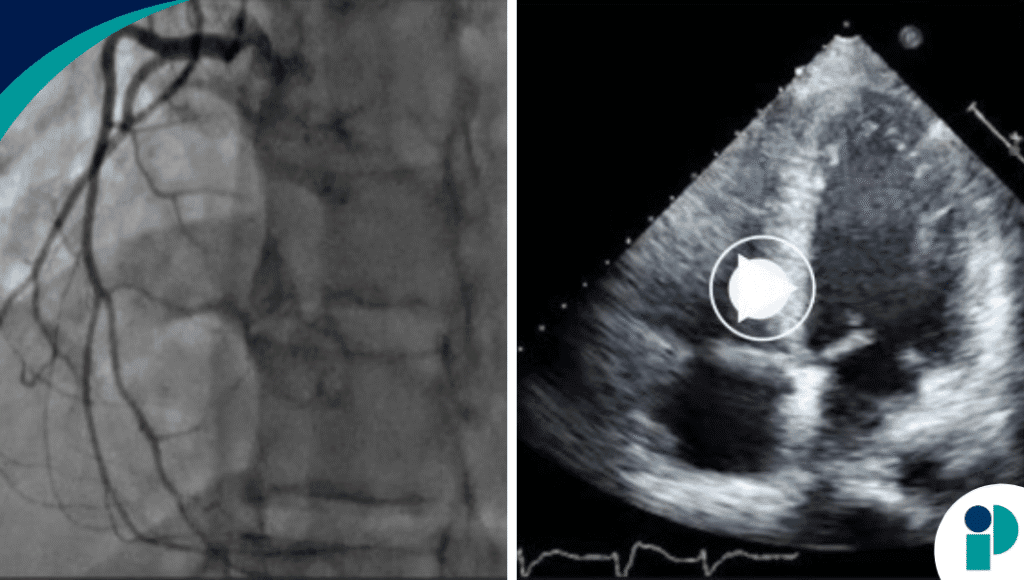

- La Ecocardiografía confirmó una fracción de eyección del ventrículo izquierdo reducida, indicativa de una función de bombeo deficiente.

- Una angiografía coronaria descartó problemas en las arterias coronarias, pero el índice cardíaco era compatible con un shock cardiogénico.